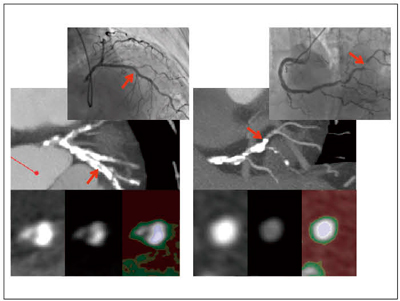

図3に,冠動脈情報と動脈硬化病変性状情報を心臓CTから得ることのできた症例を示します。distal RCAに高度狭窄病変が存在することが,CTの冠動脈長軸方向のSlab MIP像で明瞭に描出され,その部位の血管短軸に合わせた最薄のSlab MIP(実際はMPR像と同じ)では,カラーマップによってlipid coreを疑う動脈硬化病変を認めます。実際この症例では,バルーン拡張後に一時的ではありましたが,明らかなslow flowになってしまいました。

図3 冠動脈造影像とIVUS像,血管長軸方向のSlab MIP像と血管短軸方向のSlab MIP(最薄なので実際にはMPR)のカラーマップ像 血管短軸のカラーマップ像で黄に囲まれた赤のlipid coreの可能性のある動脈硬化病変を認める。

血管短軸のカラーマップ像で黄に囲まれた赤のlipid coreの可能性のある動脈硬化病変を認める。

図4には,石灰化病変を血管長軸・血管短軸のSlab MIPで観察した症例を示します。左に示すLAD病変では,石灰化部が左上と右下の2か所に分かれていること,少なくとも血管に対し同心円状になっていないことがわかり,右に示すdistal RCA病変では,石灰化が血管に対し同心円状となっていることがわかります。PCI治療の結果が上段に示されていますが,LAD病変は良好に拡張されているのに対し,distal RCA病変は高圧拡張でも拡張できず,治療不成功で終了せざるを得ませんでした。

図4 石灰化病変をSlab MIPで評価 石灰化評価には必ず,血管短軸最薄Slab MIP(MPR)像を用いる。

石灰化評価には必ず,血管短軸最薄Slab MIP(MPR)像を用いる。